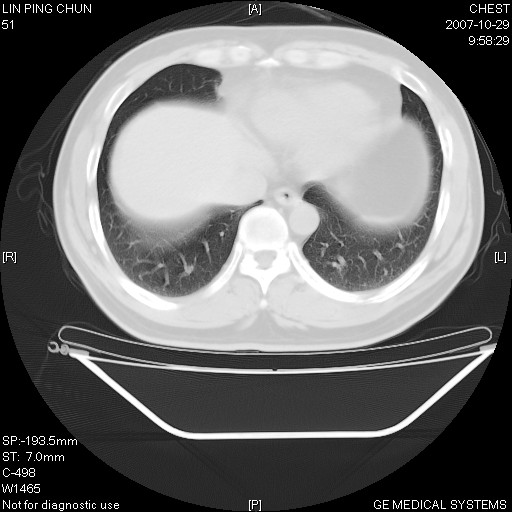

标题: CT10239:男,42Y.我自己的胸部CT扫描,今天10点突然咯血一次。

我自己胸部ct扫描,求助大家,我自己还不能给自己诊断。其他层面纵隔窗无异常。

补充:男,42y.今天10点突然咯血一次。余无异常。

左肺下叶后基底段小片结节状影,内部似见同心圆状分布条絮状影,整个病灶,质不实.局部见增粗血管影.

考虑;球形肺炎可能大.自已的身体如此重要,不进一步局部薄层及hrct?

左下肺后基底段磨玻璃样影,很多病都可以。不能吊以轻心。应该做局部增强hrct进一步检查,并严格抗炎治疗后复查或经皮活检。

左下肺后基底段小斑片泪膜玻璃样影,其内可见空泡影,边缘可见小毛刺影。建议抗炎治疗复查,肿瘤待排